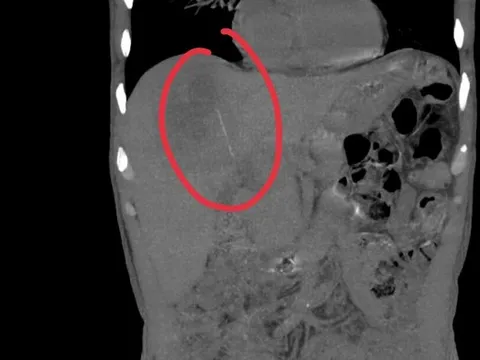

Phát hiện "thứ đáng sợ" gần 12kg trong tử cung của cô gái 25 tuổi

Cô gái trẻ có bụng to bất thường như mang thai đôi, kèm huyết khối tĩnh mạch đùi trái gần tắc hoàn toàn, tiềm ẩn nguy cơ cao thuyên tắc phổi và biến cố tim mạch khi phẫu thuật, đe dọa tính mạng.